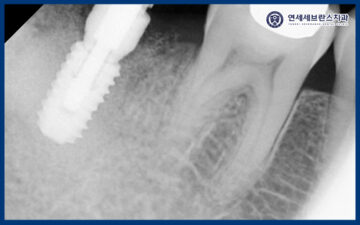

25.01.07

임플란트는 초기 고정력이

무엇보다 중요한 치료이기 때문에,

식립 후 한 달 뒤 내원하셨을 때

다시 촬영을 통해

상태를 확인하였습니다.

촬영 결과를 바탕으로

고정이 잘 이루어지고 있는지,

주변 치조골과 잇몸의 회복 상태를

세심하게 평가하였습니다.